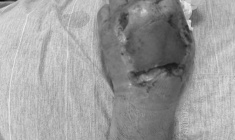

Gần đây, bệnh viện tiếp nhận nữ bệnh nhân N.T, 72 tuổi, trú tại Hải Phòng, nhập viện trong tình trạng đa chấn thương do bị chính con chó nuôi trong nhà tấn công. Con chó giống becgie, nặng hơn 30 kg, đã được gia đình nuôi khoảng 10 năm.

Theo người nhà, sau vài ngày có biểu hiện bất thường về sức khỏe, con chó bất ngờ tấn công chủ. Vết cắn kéo dài trong nhiều phút, gây tổn thương nghiêm trọng ở nhiều vị trí như cổ, thân mình và đặc biệt là vùng cánh tay trái. Tại đây, bệnh nhân bị đứt dây thần kinh giữa, mất một phần cơ lớn, lộ xương và bầm dập nặng các tổ chức phần mềm xung quanh.

Sau khi được sơ cứu tại tuyến trước, bệnh nhân được chuyển đến Bệnh viện Trung ương Quân đội 108 trong tình trạng nặng và được xử trí khẩn cấp. Các bác sỹ tiến hành phẫu thuật cắt lọc tổ chức phần mềm dập nát, nối dây thần kinh giữa bị đứt, đồng thời tiêm huyết thanh kháng dại, vắc-xin phòng dại và huyết thanh uốn ván. Con chó gây ra vụ việc hiện đã được gia đình nhốt lại để theo dõi.